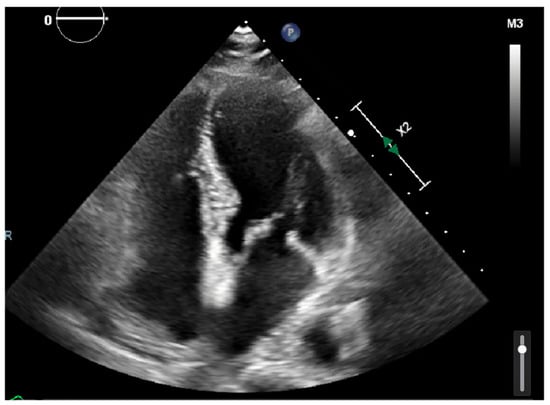

Laboratory results were as follows: WBC 8.64 K/uL (3.60–9.50), creatinine 0.8 mg/dL (0.4–1.0), TSH 1.69 uIU/mL (0.34–5.60), troponin < 0.03 ng/mL (≤0.4), D-dimer 387 ng/mL (<670), BNP < 10 pg/mL (≤106), CRP < 5.00 mg/L (≤10.00), procalcitonin 0.04 ng/mL (0.00–0.10); urine analysis negative; COVID-19 PCR infection negative; chest X-ray with no acute findings; echocardiograph with grade I diastolic dysfunction; and EF 60–65% (Figure 1 and Figure 2). EKG showed sinus tachycardia with a heart rate of 101 bpm (Figure 3). Lung CTA was observed with no significant lung pathology, and the pulmonary function test was within normal limits.

Figure 1. Echocardiography showing four-chamber view with no valvular or structural abnormalities.